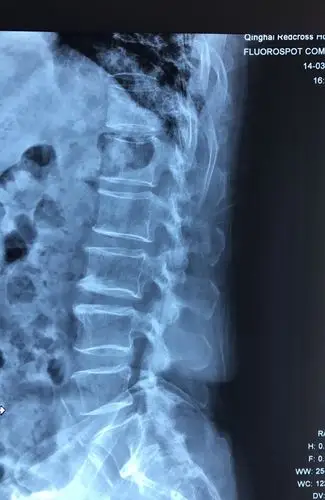

腰椎dr侧位片可以明显看出腰4/5椎间隙变窄

腰椎侧位片

这是正常的腰椎侧位x-ray,患者的腰椎侧位片显示, 腰椎生理曲度的

腰椎x线片,侧位片.